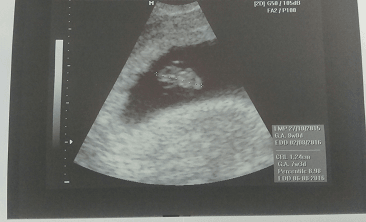

Wczoraj miałam wizytę - wszystko ok, ciąża troszkę większa, bo wszytskie pomiary pokazywały na 12+4, wszystko ok, więc ulga wielka, bardzo długo mi robił usg, mierzył i wszystko ok. Kolejne badania do zrobienia na tokspolazmoze a już sama chciałam sobie robić. Kolejna wizyta za 3 tygodnie. pokazuje zdjęcie z usg, po lewejrączka przy główce, na drugim nóżki i brzuszek![]()

dał mi zdjęcie i mówi :ma Pani swoje nóżki i rączki